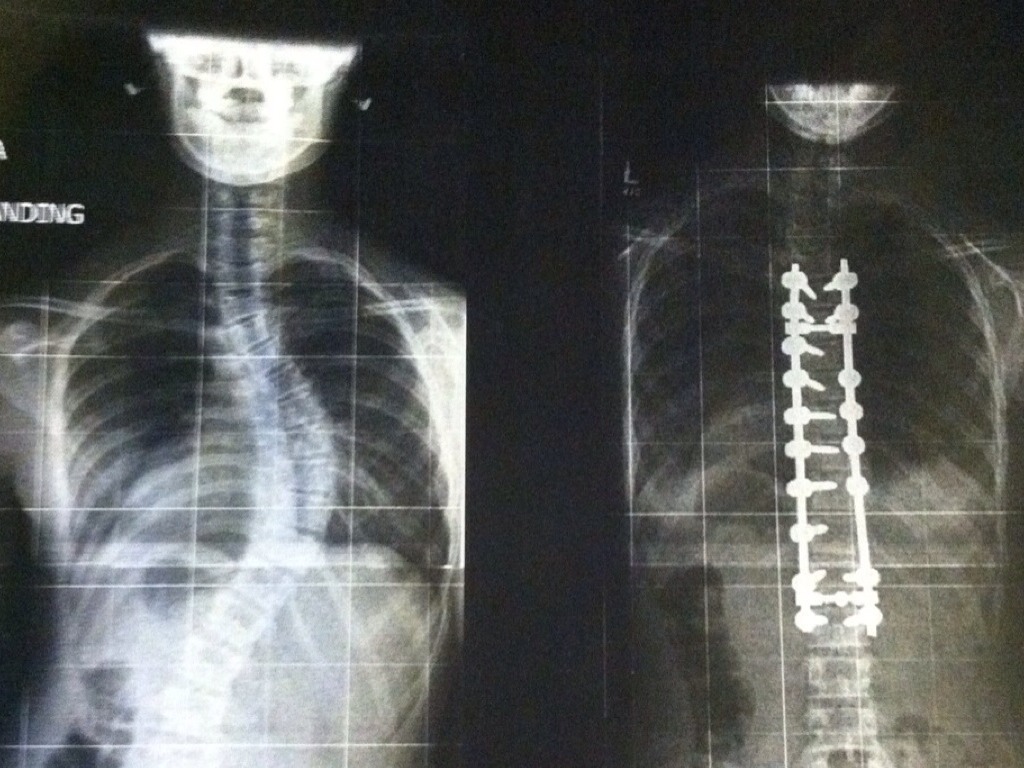

Radiology Career Information for Younger Students

CENTURY COLLEGE

BASIC SKILLS IN ANATOMY, BIOLOGY,PHYSICS, AND MATH